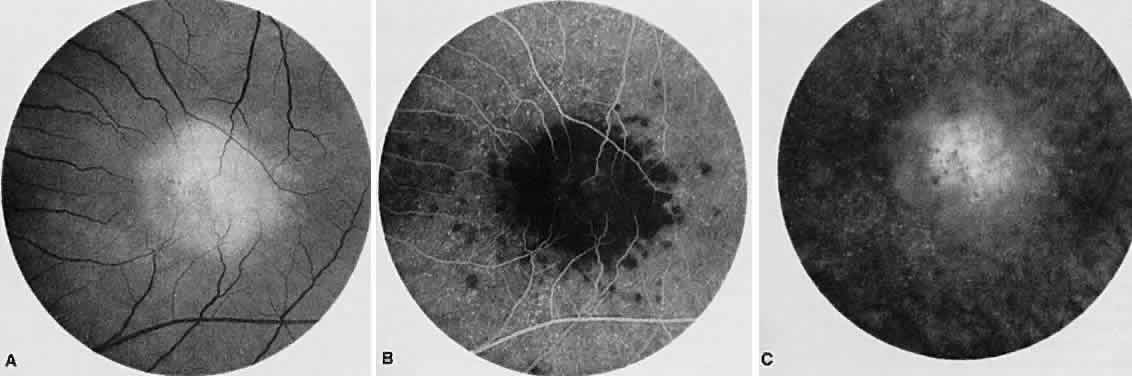

BIRDSHOT RETINOCHOROIDOPATHY

Birdshot retinochoroidopathy (also known as vitiliginous chorioretinitis) presents bilaterally, generally in middle-aged women, causing floaters and decreased vision, night blindness, and color blindness. Clinically, there are patches of postequatorial choroidal and retinal pigment epithelial depigmentation (Fig. 10A), vitreous cells, macular and disc edema, and venous sheathing. SRNV frequently is a late sequela. Often central vision may be preserved in at least one eye.

Fig. 10. Birdshot retinochoroidopathy. A. Multiple cream-color deep choroidal lesions. B. Fluorescein angiogram shows leakage of the optic disc and the retinal vasculature. C. Indocyanine green angiography showing areas of hypofluorescence that exceed those observed on fluorescein angiography.

On fluorescein angiography, retinal vessel staining, disc leakage, and cystoid macular edema are found (see Fig. 10B). There often is generalized hypofluorescence of the retinal vessels and increased circulation time.35,36 Surprisingly, the patches of depigmentation may appear normal on angiography, although there can be mild late hyperfluorescence.35,36 Posterior pole choroidal hyperfluorescent lesions that correspond to the areas of depigmentation and SRNV also can be seen.37

On ICG angiography (see Fig. 10C), early and late hypofluorescent patches, exceeding the clinically detectable lesions, with a choroidal vasotropic distribution and relative sparing of the peripapillary area and the central macula, are noted. These findings differentiate this condition from AMPPPE, multifocal choroiditis, and other granulomatous conditions such as sarcoidosis and sympathetic ophthalmia. Rarely, hyperfluorescent spots are noted in the late phases of the angiogram, which correspond ophthalmoscopically to retinal inflammation or obstructive changes.38